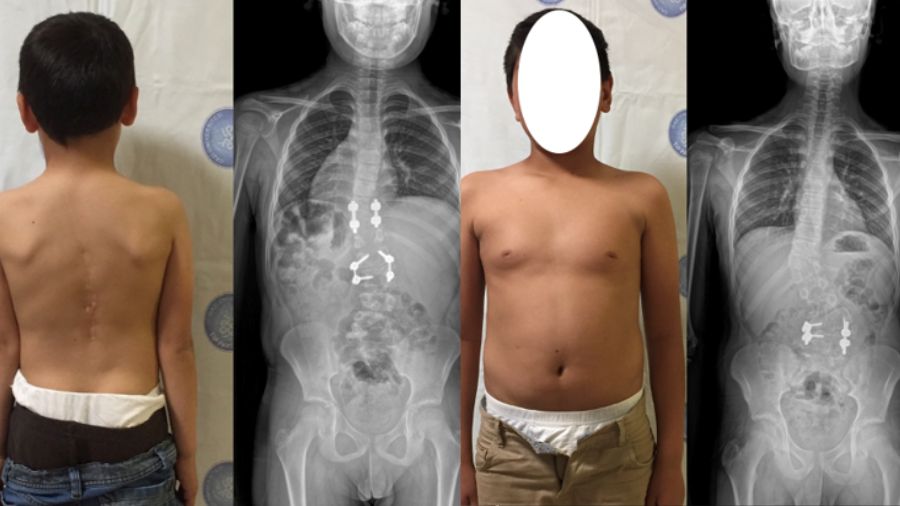

The boys both had contralateral hemivertebra, but with differing degrees of severity, and I followed different treatment strategies for the two patients. The younger boy had a hemivertebra in the middle of the lumbar spine, at L-2, and another in the lower thoracic spine around T-10. The older patient had similar deformity pattern with contralateral lumbar and thoracic hemivertebrae. These patients live in a rural area, otherwise it is likely that the spinal deformity would have been picked up at an earlier stage. Congenital scoliosis can cause a severe deformity of the spine, leading to problems such as respiratory insufficiency and neural impairment.

In the case of these brothers, the older brother’s deformity was relatively well controlled, and upper curvature was quite mild, whereas both curves of younger boy were high magnitude. For the younger sibling I was able to excise both hemivertebrae. With localized problems like this, say two or maximum three segments, we are often able to perform a short segment fusion and excision. If we were to wait for excision of the hemivertebra for a long time, we may end up with a reciprocal change in spinal column and necessity of long fusion construct. By taking action earlier we can arrive at a solution with very limited surgeries and without jeopardizing their maturation and growth.

Surgical revision may be necessary as patient reaches adolescence

At the follow-up scans, we found that the younger sibling had recovered very well, and his spine was well aligned. For the older brother, I only removed one hemivertebra, and decided to follow the progress of the other. At the follow-up scans he is not so well aligned - in fact the upper thoracic vertebra is totally unbalanced, creating a deterioration of the curvature in the thoracic part. This is clearly evident in the radiographs but in terms of clinical appearance, he looks fine as you can see in the picture.

At that point, I talk to the patient and offer a surgical revision. In this case, because the boy appears to be well balanced, they decide it’s not needed, but I will still follow how this case progresses over a period of 10 years. If there is more deterioration, we may have to consider another revision surgery.